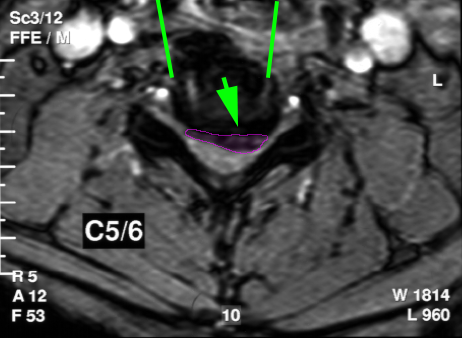

Περιγραφή Η επέμβαση γίνεται υπό γενική αναισθησία με οριζόντια τομή λίγων εκατοστών στο δεξί συνήθως μέρος του λαιμού. Ο μεσοσπονδύλιος δίσκος ο οποίος πρόκειται να αφαιρεθεί εντοπίζεται με την βοήθεια ακτινοσκόπησης, και στην συνέχεια εξαιρείται σε τεμάχια, με την βοήθεια χειρουργικού μικροσκοπίου, έως τον σπονδυλικό σωλήνα. Αφαιρούνται επίσης και τυχόν συνυπάρχοντα οστεόφυτα τα οποία πιέζουν τον νωτιαίο μυελό ή τα αυχενικά νεύρα. Η δισκεκτομή ακολουθείται από σπονδυλοδεσία με κλωβό ή αρθροπλαστική με τεχνητό αυχενικό δίσκο. Αντενδείξεις και Επιπλοκές Ουσιαστικές αντενδείξεις της πρόσθιας αυχενικής δισκεκτομής δεν υπάρχουν. Οι πιο συνήθεις επιπλοκές είναι η μετεγχειρητική δυσφαγία και δυσφωνία από την διεγχειρητική παρεκτόπιση και πίεση του οισοφάγου και του παλίνδρομου λαρυγγικού νεύρου, οι οποίες είναι κατά κανόνα προσωρινές. Επιδείνωση του νευρολογικού ελλείμματος, ειδικά στους ασθενείς με αυχενική μυελοπάθεια, μπορεί να παρατηρηθεί σε μικρό ποσοστό, αλλά είναι και αυτή στην πλειοψηφία των περιπτώσεων προσωρινή. Αστοχία του συστήματος σπονδυλοδεσίας (μετατόπιση υλικών) συμβαίνει σε ποσοστό 0,5%. |

Πρόσθια αυχενική μικροχειρουργική δισκεκτομή σε ασθενή με αυχενική δισκοκήλη. Η τραχεία (πράσινο), ο οισοφάγος (κίτρινο) παρεκτοπίζονται αριστερά (κόκκινα βέλη) και για να δημιουργηθεί το κανάλι προσπέλασης στον δίσκο (κυανές γραμμές). Ο δίσκος αφαιρείται και κατόπιν εξαιρείται και η δισκοκήλη(μωβ). Οι καρωτίδες είναι οι δύο κόκκινοι κύκλοι εκατέρωθεν της προσπέλασης.